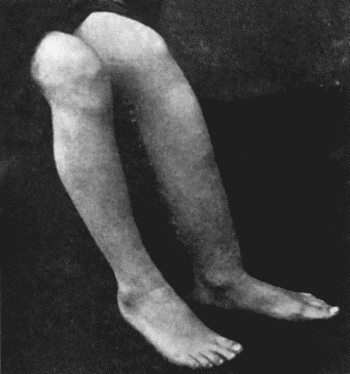

| 135. | Cadaver, illustrating the alterations in the Lower Limbs resulting from Ostitis Deformans | 475 |

| 49. | Zanthoma of Buttock | 189 |